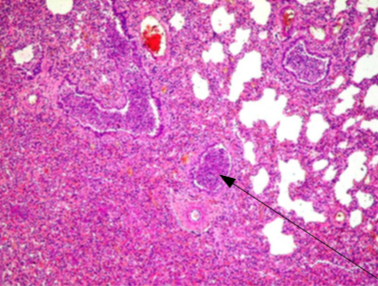

Identify lesion

Bronchopneumonia

identify lesion:

What changes can be observed in this lesion and what are the 4 Stages?

-Multifocal changes-

Four stages, but we can observe different stages in every focus.

Pneumonia has 4 stages:

Congestion

Red hepatization

Gray hepatization

Resolution